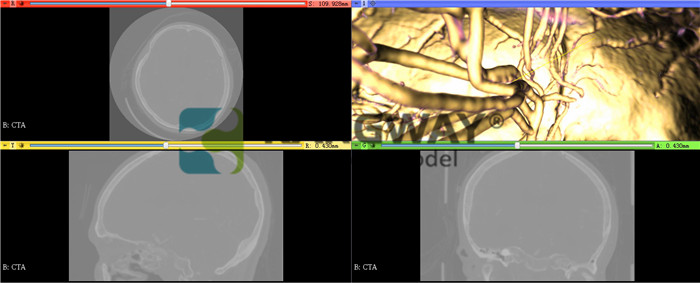

7.圖像處理高級功能

(1)支持MPR重建;

(2)支持MIP重建,可以選擇最小值,平均值和最大值進行重建;

(3)支持虛擬3D容積重建功能,支持各個方向旋轉三維圖像;

(4)支持超過20種3D重建預設;

(5)支持多平面重建,能同時顯示橫斷、冠、矢位圖像,并能夠同步調整和顯示;